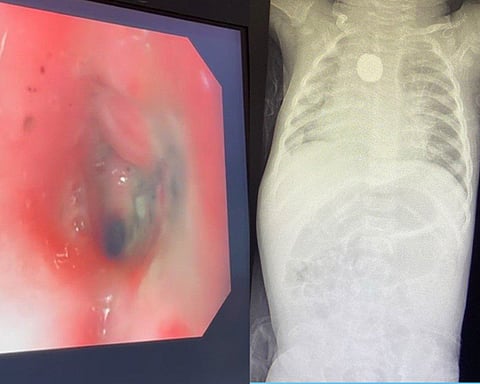

وأضاف، تبيَّن وجود حروق داخل المريء مع تضيُّق المنطقة المتأثرة وعدم رؤية الجسم الغريب مبدئياً وبعد محاولات عدة اتضح وجوده ملتصقاً ومغطى بأغشية الجدار داخلياً؛ ما أتاح إمكانية سحبه بالمنظار بسلامٍ دون حدوث ثقبٍ أو نزيفٍ في المنطقة ذاتها، وجرى إدخال المنظار مرة أخرى، والتأكد من عدم وجود ثقب أو تسرُّب هوائي داخل الصدر.

وأوضح تجمُّع مكة المكرّمة الصحي، أن الطفلة حضرت إلى قسم الطوارئ كحالة إنقاذ حياة، وهي تُعاني التهاباً متكرراً في الحلق منذ شهر، ومع مُضي الأيام أصبح البلع لديها صعباً ولم تتمكن من البلع العادي منذ أكثر من خمسة عشر يوماً، وعلى الفور أُجريت الفحوصات اللازمة، حيث جرى اكتشاف جسمٍ غريبٍ؛ ما استدعى التدخل الطبي العاجل لإنقاذ الطفلة، وتمّ تكوين ثلاث فرق طبية لاستخراج البطارية الحارقة دون حدوث مضاعفات، متمثلة في فريق قسم المناظير، وجراحة القلب والشرايين، وجراحة الأطفال، وتبيّن من خلال الأشعة المقطعية وجود الجسم الغريب على مقربة من شرايين القلب، مختفياً في جدار المريء مع الضغط على الحنجرة المجاورة.